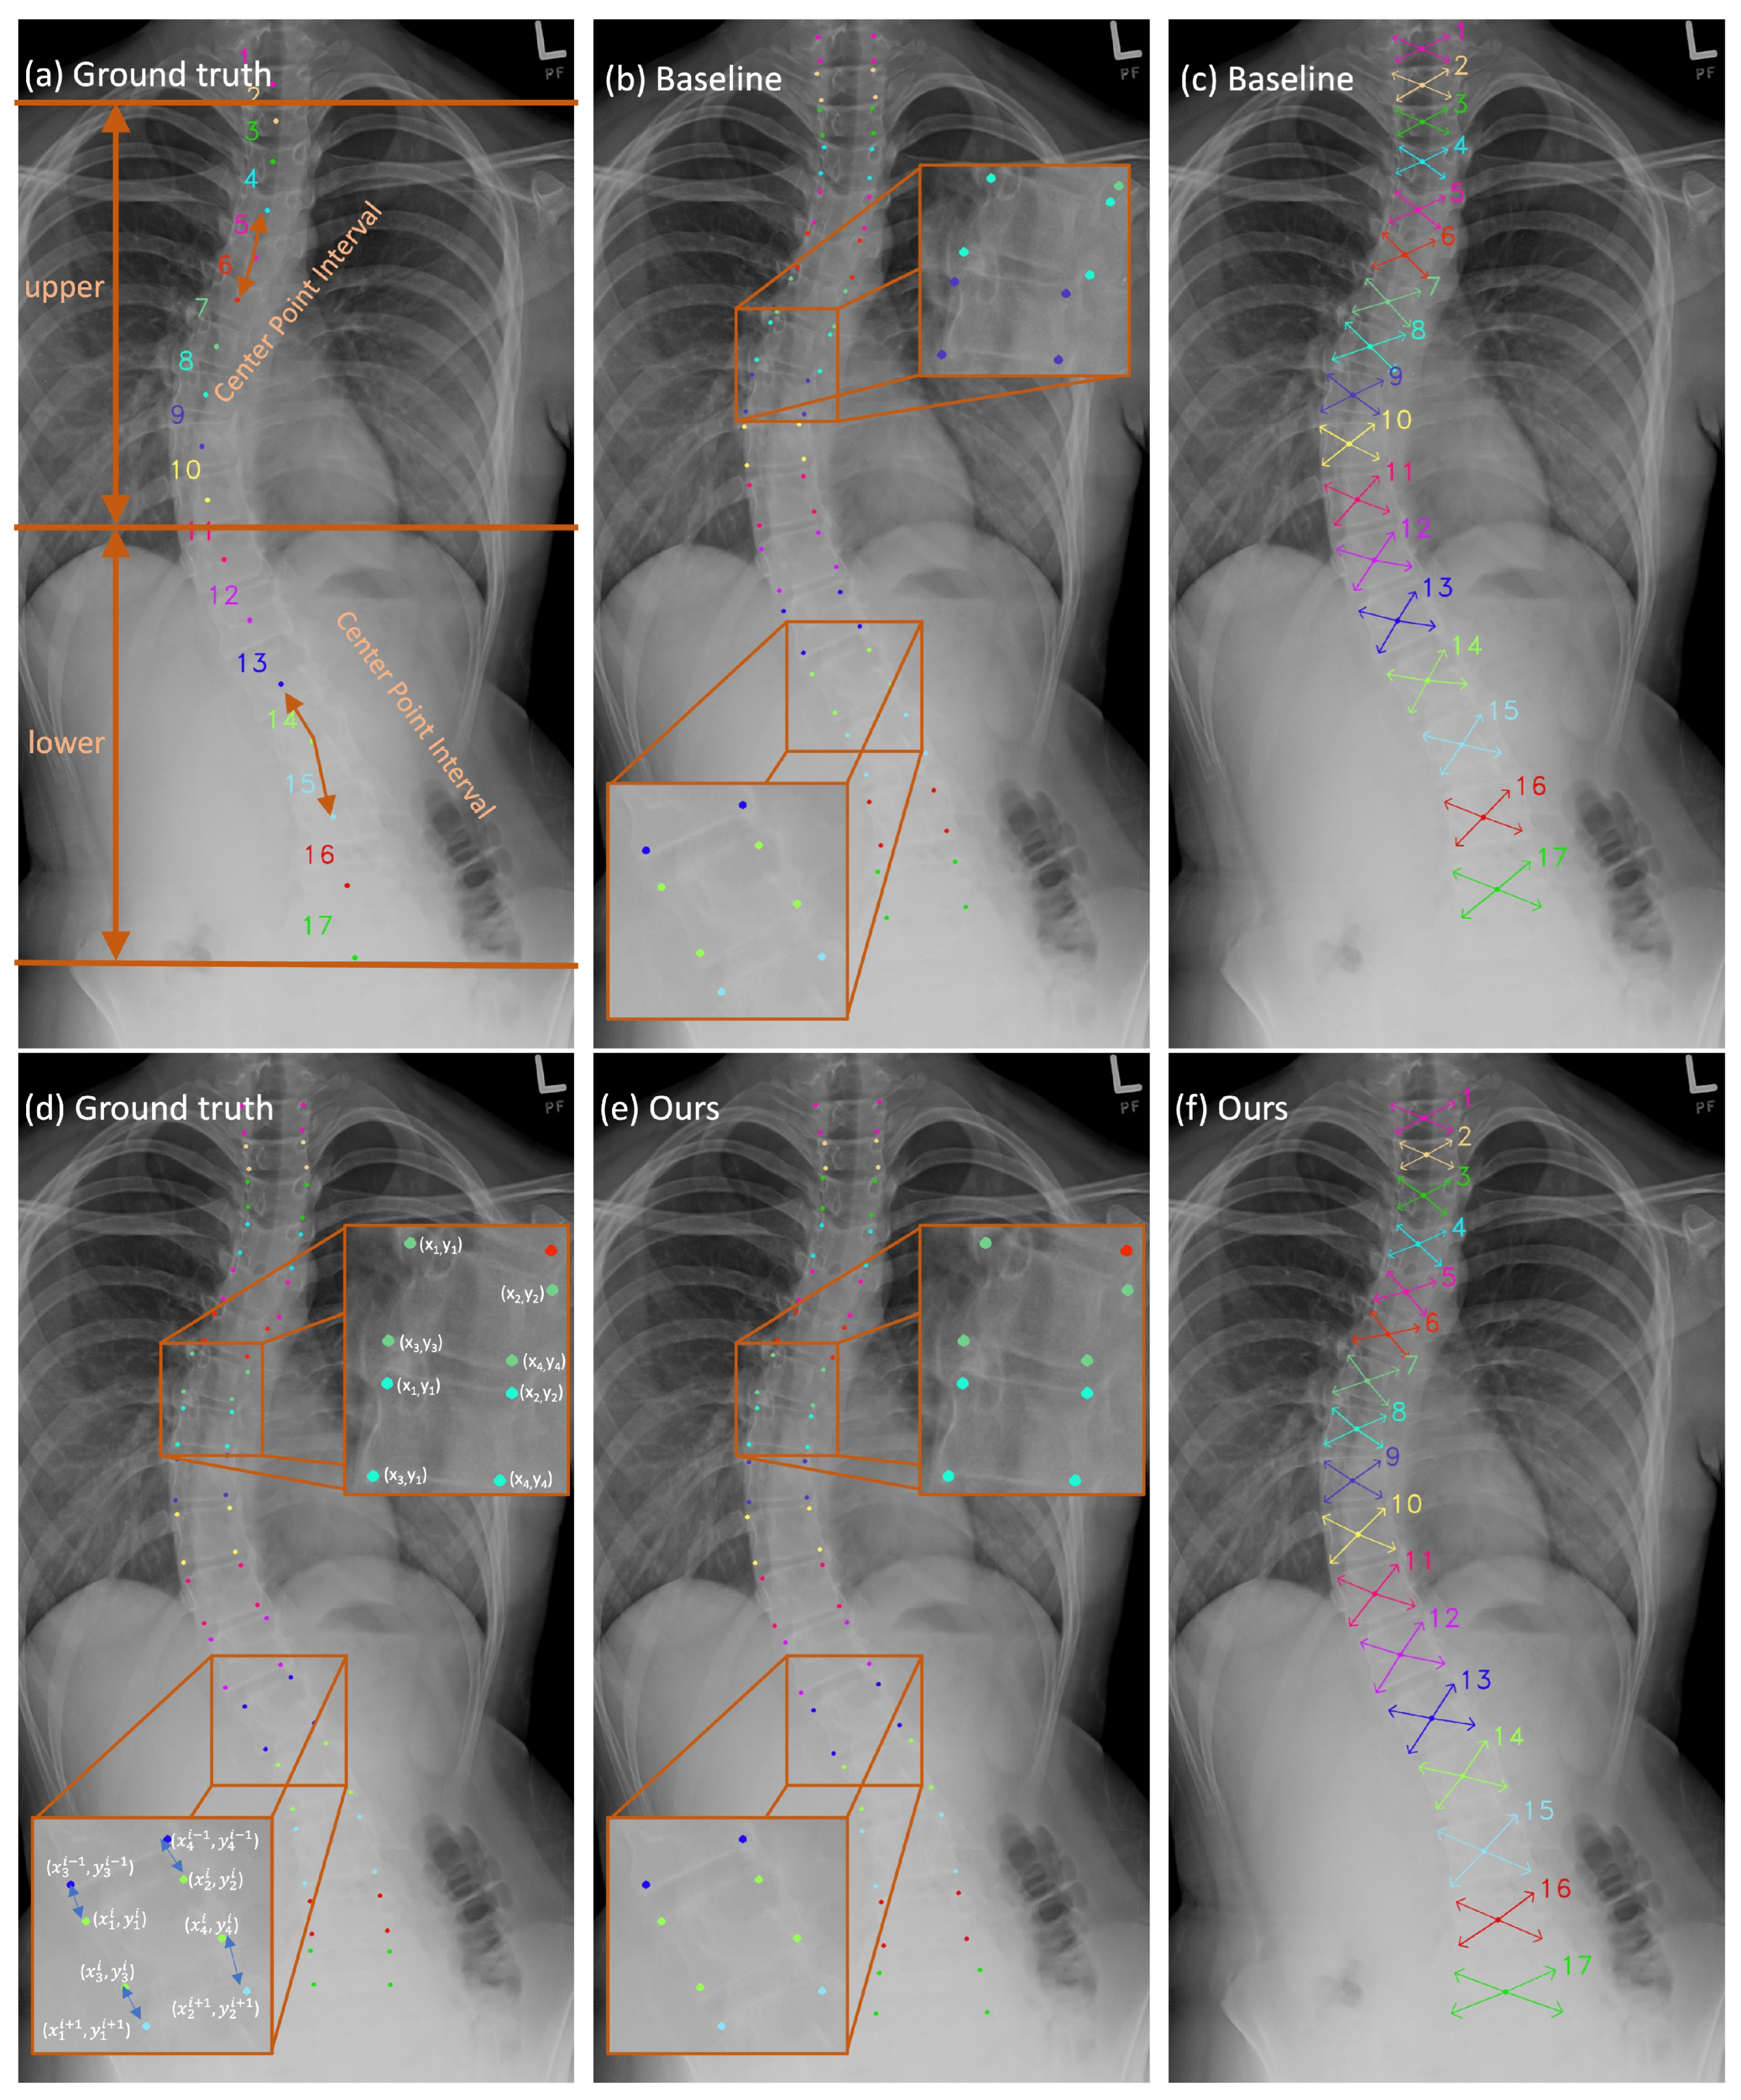

- We introduce an effective scheme, namely the center point interval estimator (CPIE), as an approach to obtain inter-vertebral supervision information to estimate the center points of vertebrae. The proposed scheme enhances the precision of center point localization, particularly in cases where vertebrae are subject to significant background interference. This improvement effectively reduces the accumulation of errors caused by inaccurately identified center points.

- We introduce a novel approach using a dual coordinate system during the learning process. Our strategy involves the utilization of both Cartesian and polar coordinate systems for presenting the ground truth of center points and corner offsets, respectively. The sub-tasks can effectively preserve the advantages to a greater extent by using multiple coordinate systems.

- We introduce a vertebral line interpolation scheme to alleviate the drawbacks of the ground truth design during the network training process by converting the ground truth from sparse to dense.